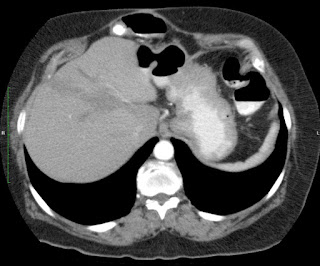

Paciente de 66 años con antecedente de pancreatitis, tomografía control.